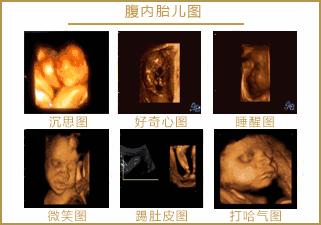

“宫内5D电影”其实就是通过5彩超实时动态地显示胎儿在子宫内的情况,先来组静态图,虽然是静态,但看得更清楚,图片也足够惟妙惟肖,必定能激发起您的想象力哦!

再看看这张动态图片,通过5D彩超,孕妈可以看到胎宝在腹中微笑、吮手指、踢腿、伸懒腰、打哈欠,通过它可以捕捉到宝宝在母体内的一举一动